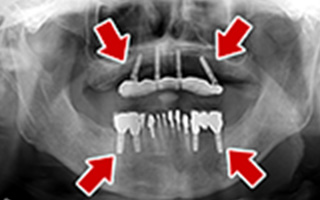

Before

After

| 55歳 男性 | |

|---|---|

| 主訴 | 前歯でしか咬めなく、食事を摂るのに非常に困難で辛い |

| 処置内容 | 上顎6本、下顎3本 |

| 治療費用 | 上顎: 約230万(税込) 下顎: 約120万(税込) |

| 治療期間 | 上顎: 1年(仮歯まで8ヶ月) 下顎: 8ヶ月(仮歯まで5ヶ月) |

| リスク | 上部構造物、仮歯の破折、術後の腫れ(3日)、人工歯根脱落リスクがあります |